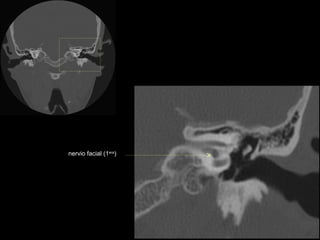

CATEDRA DE RADIOLOGIA U.N.L.P.   Hueso temporal normal              Edición 2002

seno maxilar

conducto

carotídeo

auditivo externo

protuberancia

occipital externa

trompa de Eustaquio

conducto auditivo externo

celdillas mastoideas

eminencia piramidal

seno timpánico

receso del n. facial

nervio facial (3era)

estribo (cruras)

nervio facial

ventana oval

martillo

yunque

cóclea

vestíbulo

conducto semicircular externo

articulación yunque/martillo

conducto auditivo interno

conducto semicircular posterior

antro mastoideo

celdillas retrolaberínticas

conducto semicircular

superior

conducto semicircular superior

cabeza del martillo

procidencia de meninges

tendón tensor del tímpano

conducto carotídeo

espina supra y retrotimpánica

nervio facial (2da)

nervio facial (1era)

cresta falciforme

promontorio

estribo

membrana

timpánica

externo

ventana redonda